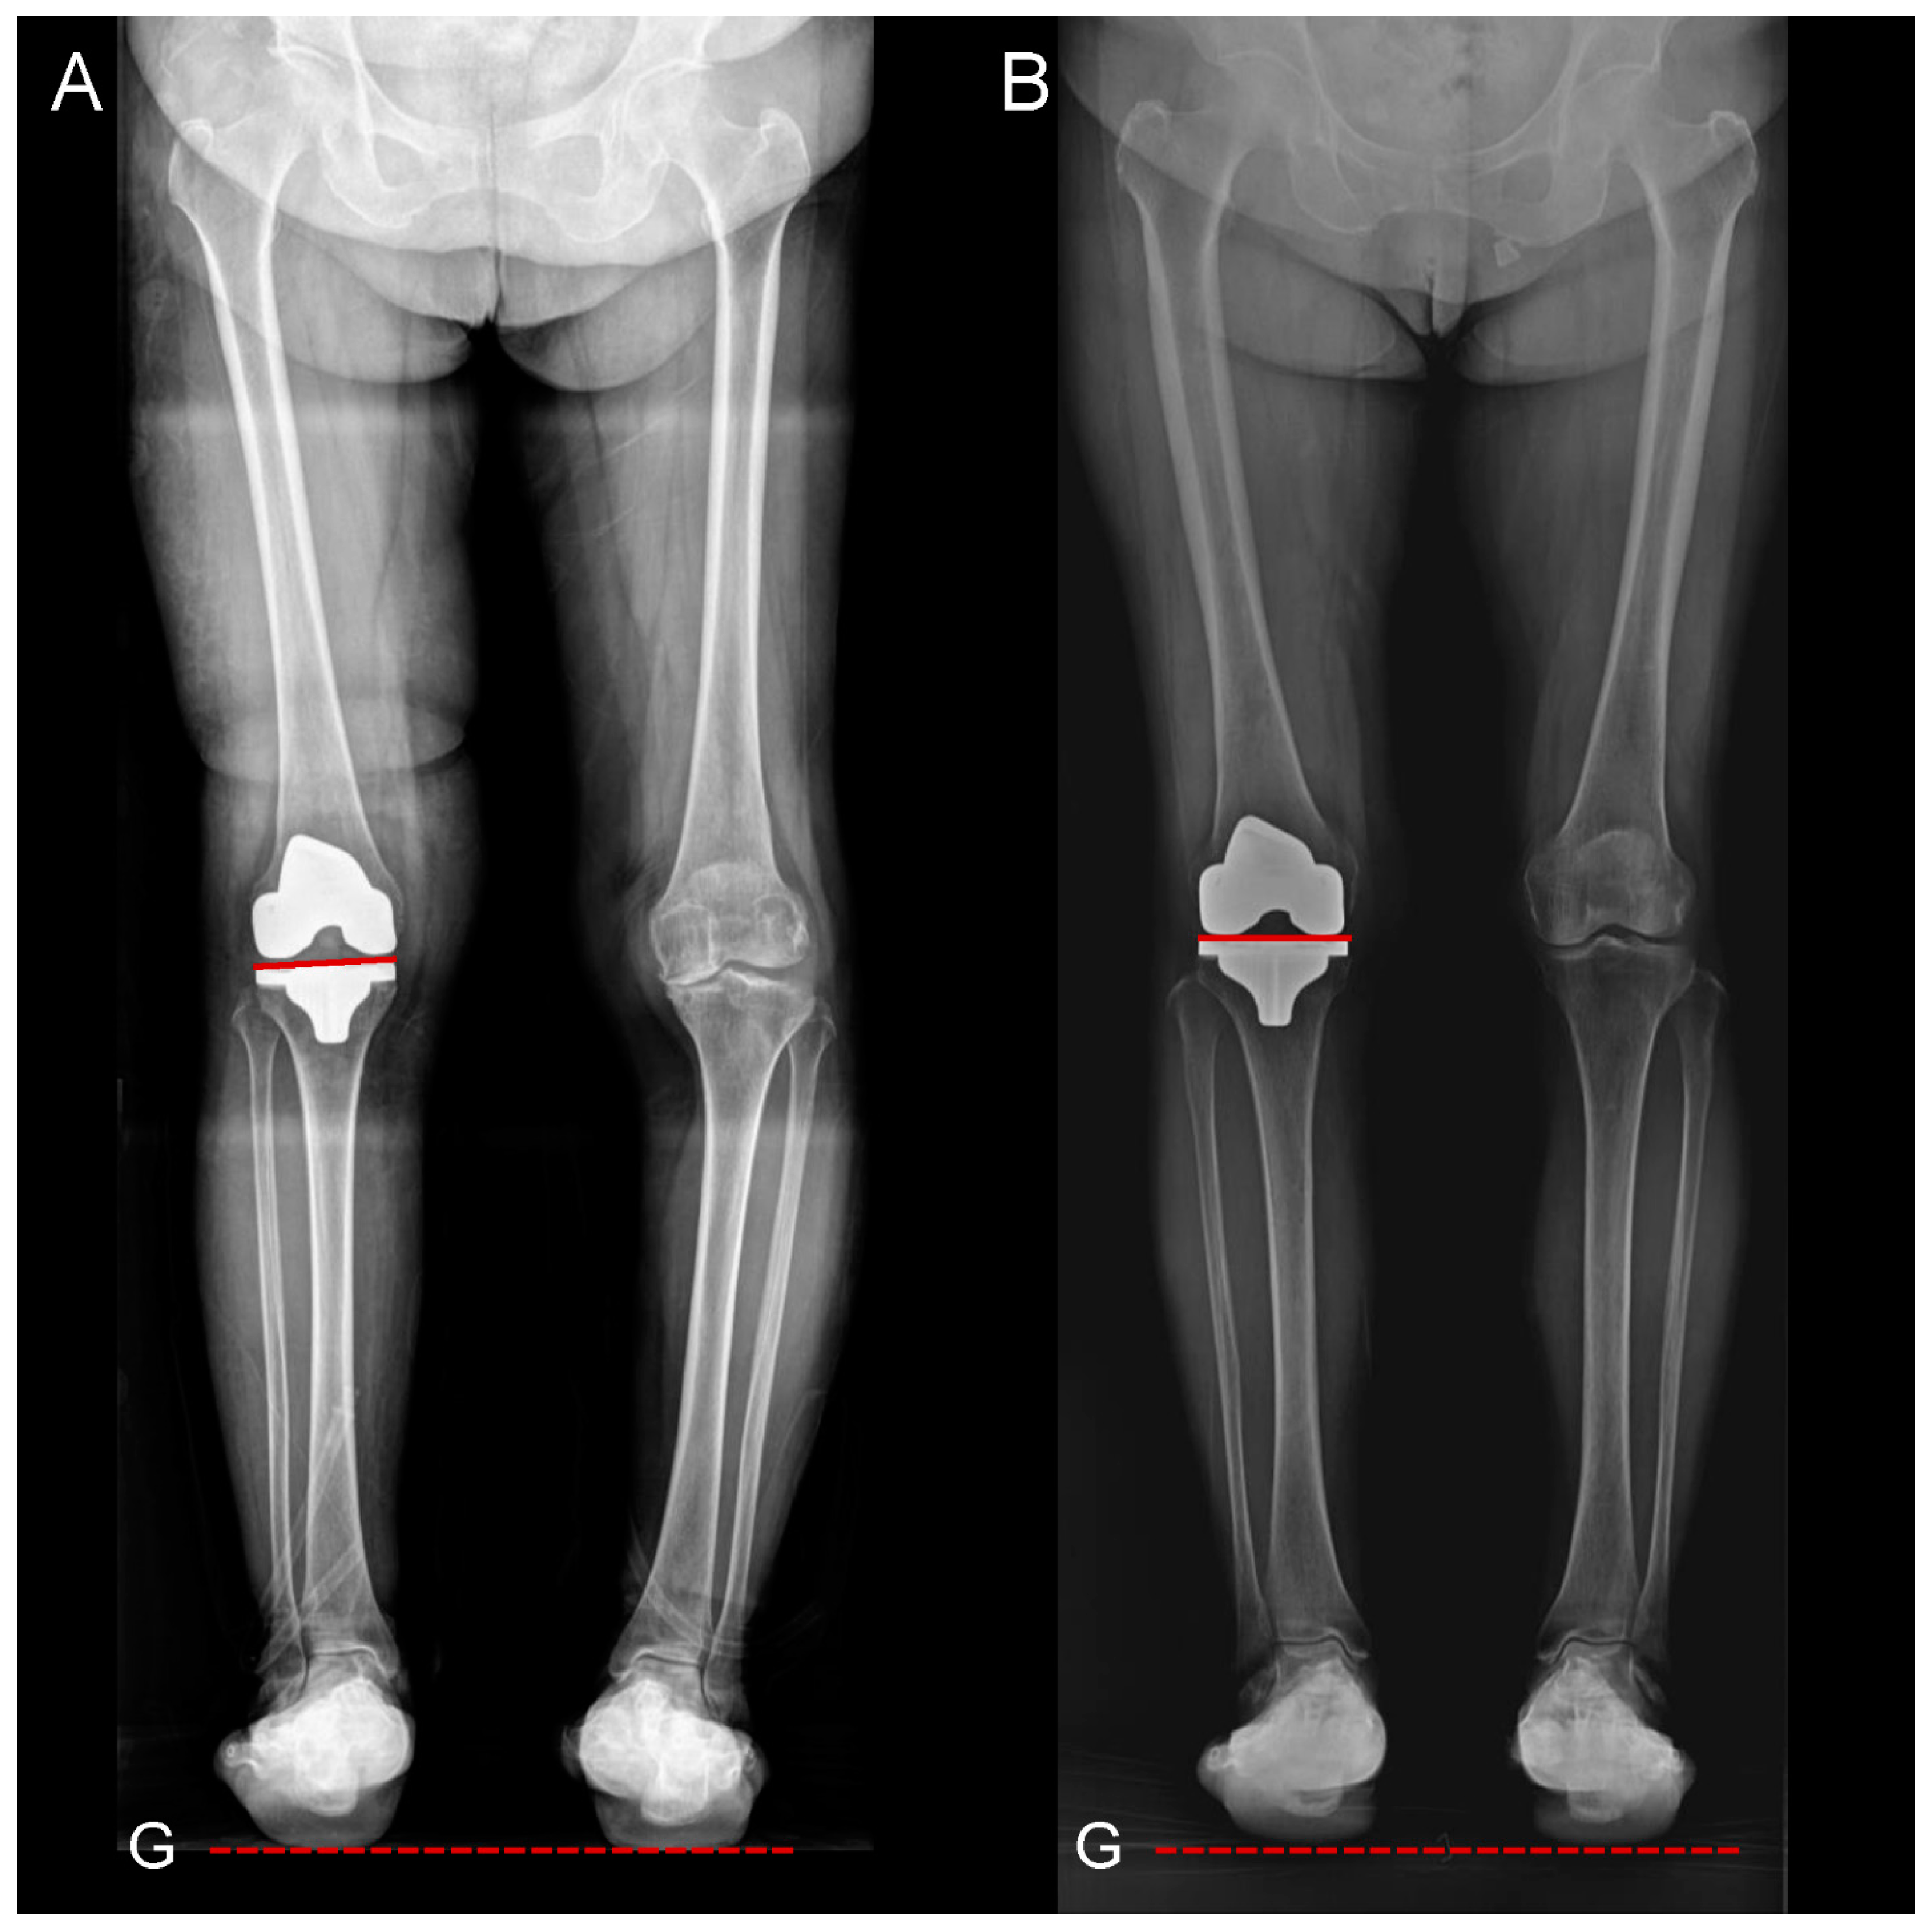

2.3. Radiographic Assessment

| Weight-bearing position in the knee joint § | |||

| Traditional MA ratio | 42.6 ± 7.6 | 48.3 ± 8.0 | <0.001 |

| GA ratio | 48.8 ± 7.0 | 53.8 ± 8.8 | 0.002 |